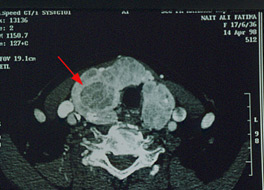

Le Scanner

Il a peu d’intérêt dans le « nodule simple » mais trouve sa place dans le bilan d’extension des cancer et dans les volumineux nodules compressifs.

Scanner: Volumineux nodules hypodense (flèche) au sein d’un goitre